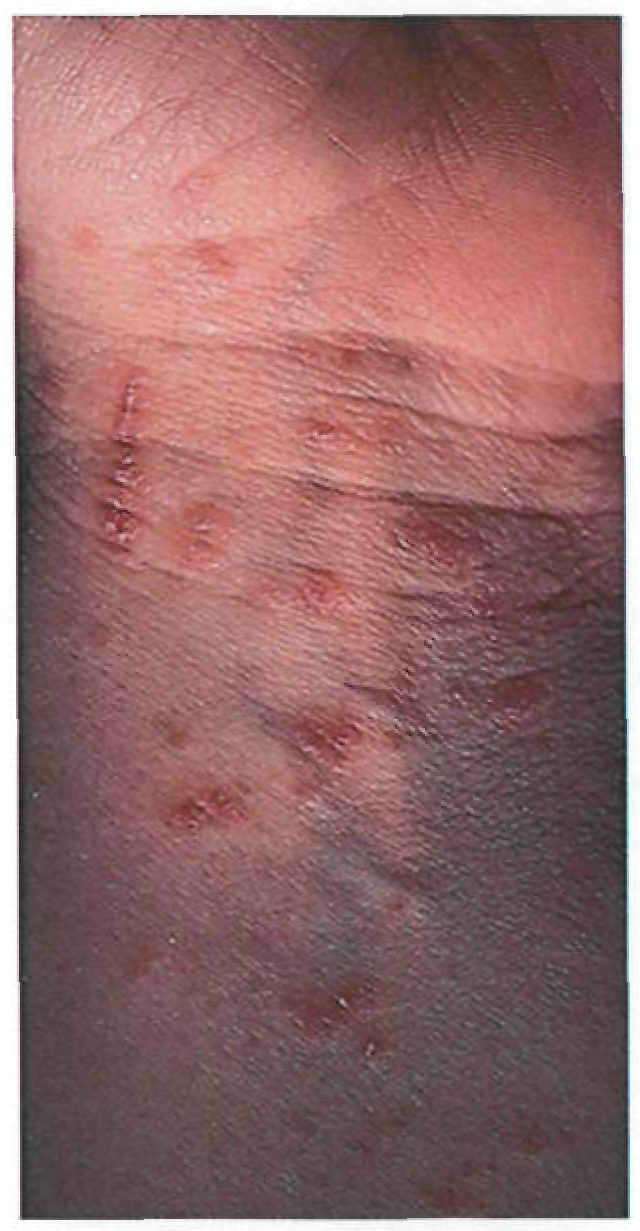

Период высыпаний

На 3-4-й день болезни температура тела снижается до субфебрильной, одновременно на коже головы (прежде всего на лице) и на слизистых оболочках полости рта, гениталий, конъюнктивы, роговицы глаз появляются необильные элементы сыпи. Энантема на слизистых оболочках полости рта обычно предшествует появлению экзантемы. Первые элементы сыпи обычно появляются на лице, быстро распространяясь на верхние конечности, а затем - на туловище и нижние конечности, поражая ладони и подошвы. Распространение экзантемы имеет центробежный характер - на туловище элементов меньше, чем на лице и конечностях.

Высыпания эволюционируют через стадии:

- макула (пятно) (1-2 дня);

- папула (узелок) (1-2 дня);

- везикула (пузырек, заполненный прозрачной жидкостью) (1-2 дня);

- пустула (гнойничок) с пупковидным вдавлением в центре (5-7 дней);

- корочка (7-14 дней).

В 95% случаев сыпь поражает лицо, в 75% - ладони и подошвы, что является отличительным признаком заболевания. Также поражаются слизистые оболочки полости рта (в 70% случаев), половые органы (30%), конъюнктива и/или роговица (20%). У части пациентов имеет место проктит с поражениями перианальной области изолированно или в сочетании с высыпаниями в области гениталий [39]. Количество элементов сыпи варьирует от единичных до нескольких тысяч [13].

Согласно данным ВОЗ у многих пациентов с МРХ, выявленных в 2022 г. в неэндемичных по данному заболеванию странах, заболевание протекает в атипичной форме, включающей следующие признаки: появление небольшого количества элементов сыпи или только одного элемента, которые возникают в области гениталий или промежности и не распространяются на другие участки кожи; наличие очагов поражения кожи на разных (асинхронных) стадиях развития; появление сыпи до начала увеличения лимфатических узлов, лихорадки, недомогания или других симптомов [41].